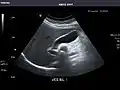

Abdominal ultrasound can be used to diagnose abnormalities in various internal organs, such as the kidneys,[1] liver, gallbladder, pancreas, spleen and abdominal aorta. If Doppler ultrasonography is added, the blood flow inside blood vessels can be evaluated as well (for example, to look for renal artery stenosis). It is commonly used to examine the uterus and fetus during pregnancy; this is called obstetric ultrasonography.[2][3]

Through the abdominal wall, organs inside the pelvis can be seen, such as the urinary bladder or the ovaries and uterus in women. Because water is an excellent conductor for ultrasound waves, visualizing these structures often requires a well-filled urinary bladder (this means the patients has to drink plenty of water before the examination).